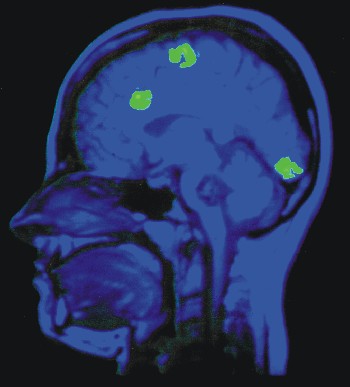

Links sind zwei Bilder überlagert: Ein Kernspintomogramm des Kopfes (blau) und ein Positronenemissions-Tomogramm (PET; grüne Flecken), das erhöhte Gehirnaktivität in drei Bereichen anhandt erhöhter Stoffwechselaktivität darstellt. Die Bilder sind weder gleichzeitig aufgenommen worden, noch stammen sie vom selben Menschen. Die Kernspinaufnahme dient lediglich zur Identifizierung der aktiven Hirnareale. Die räumliche Auflösungen von NMR- und PET-Signalen liegen im Bereich von 1 mm (NMR) bis 7 mm (PET). Beim PET können mit einer besonderen Art von Kontrastmittel (Positronenstrahlern) Stoffwechselwege verfolgt und der lokale Energieverbrauch gemessen werden. Die Registrierung eines Bildes kann einige Sekunden bis Minuten beanspruchen.

Aus: Kandel, E.R., Schwartz, J.H., Jessel, T.M. (1991)